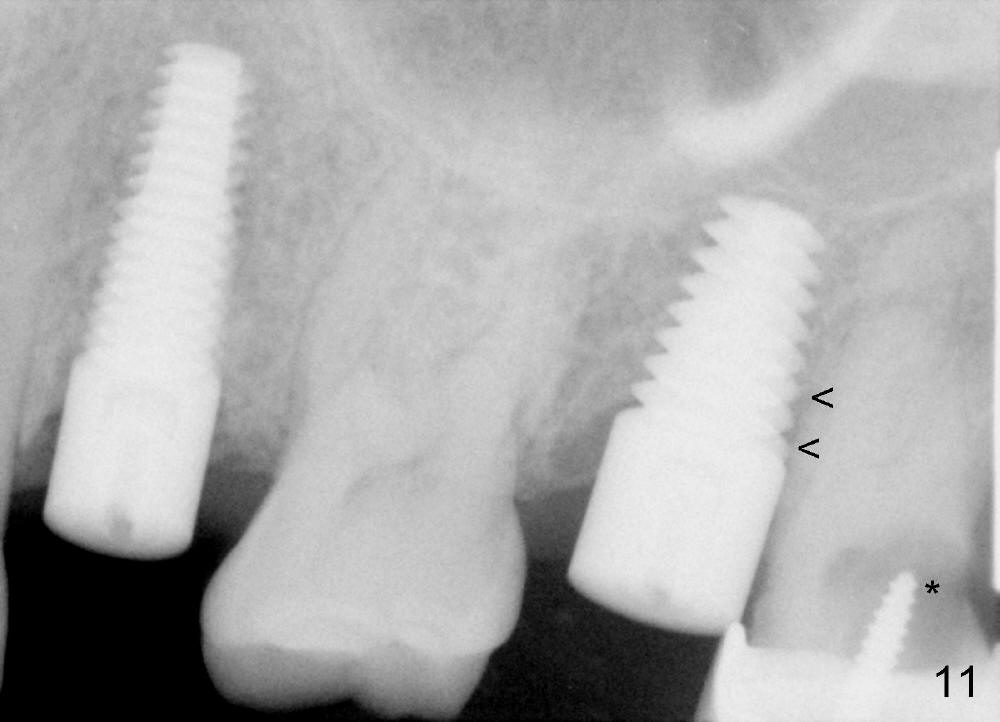

A 43-year-old lady has multiple nonsalvageable teeth. The first surgery involves two immediate implants in the upper left sextant (Fig.1: #13 and 15). The tooth #15 has 3 residual roots (MB, DB, P). There is no septum left between the first two roots when the tooth is extracted. A septum exists between the palatal (P) and buccal (B) sockets (Fig.2). Bone expansion technique is utilized to create an osteotomy in the septum. However, the smallest rounded tapered osteotome cannot be driven into the narrow septum; it slides (Fig.5). To get an initial engagement, a slot is created by high-speed surgical handpiece and fissure bur on the top of the septum. A series of blade-like osteotomes are inserted into the septum for sectioning (Fig.2 >). The smallest rounded osteotome is now easy to be inserted into the middle of the septum (Fig.3 circle, Fig.6 O). The septum is expanded by larger osteotomes (Fig.4 white circle; Fig.7 O) and tap (Fig.9 T). The septum continues being expanded when a 6x14 mm implant is placed (Fig.8,10 I). The insertion torque is more than 60 Ncm. No bone graft is placed. The palatal gap is closed by a palatal flap.

Postop, the patient has a car accident. She does not return for followup until 11 months later. The implant is stable. The neighboring third molar has caries (Fig.11 *). When it is extracted, the distal threads of the implant are found to be exposed (apical to ^ in Fig.12). A synthetic bone graft is placed to cover the exposed threads, followed by insertion of a collagen plug (Fig.13).